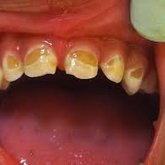

Hermanus-based, Dr Righardt van Huyssteen is a dental practitioner with more than 15 years of dental experienc...